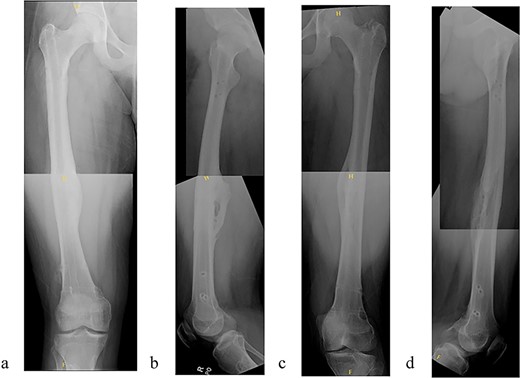

The patient underwent sequential bilateral trochanteric entry antegrade femoral intramedullary rods (Stryker, Kalamazoo, MI, USA) after utilizing bilateral RIAs. We first passed the 8.5-mm end-cutting reamer from the RIA system (DePuy Synthes, Solothurn, Switzerland) and then upsized to an 11.5-mm reamer (Fig. 3a–d). We used the same reamers to prepare the contralateral side.

(a) Obtaining greater trochanteric entry starting point. (b) Fracture reduction with the “F” tool and passed ball-tipped guidewire. (c) Sequentially reaming with the RIA. (d) Maintained fracture reduction with implanted rigid femur rod.